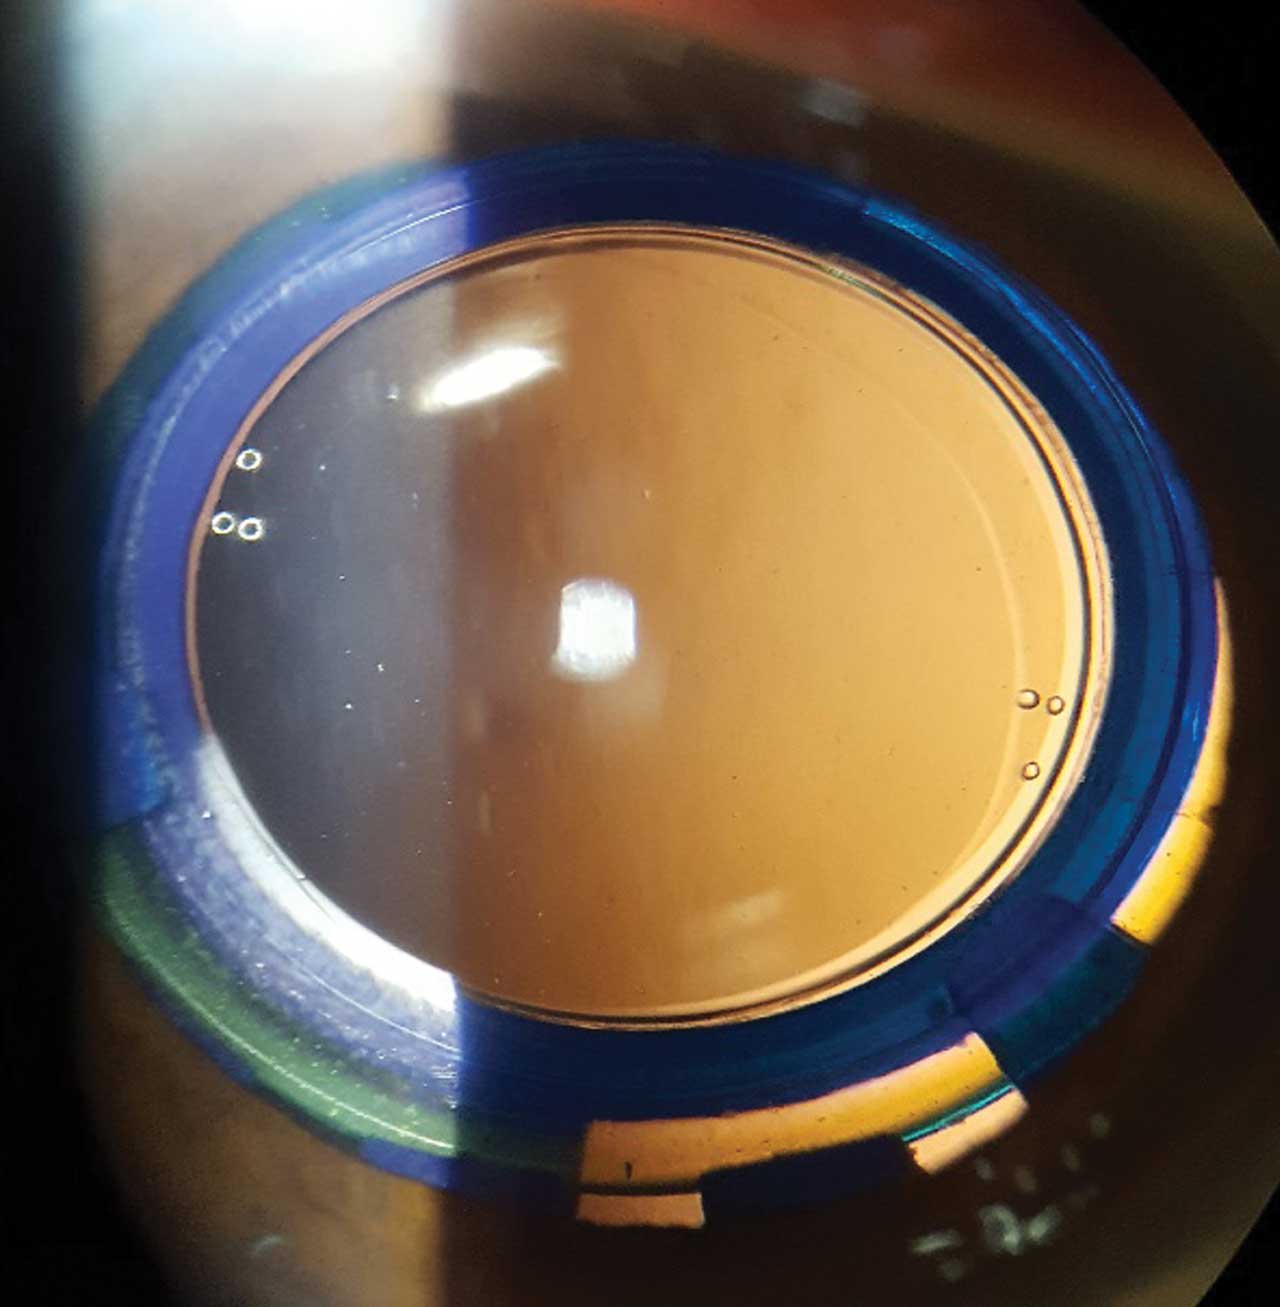

A modular, curvature-changing IOL, Juvene (LensGen, Inc.) improves vision at all distances, and outcomes remain stable 1 year after implantation. This novel IOL is comprised of a base lens that is supported by circumferential silicone haptics that fill the capsule, similar to the natural crystalline lens, and a fluid lens that fits into the base lens and facilitates a continuous range of focus from distance to near. The two lenses are modular and can be implanted through a relatively small incision. The silicone base lens goes into the capsular bag, and the refractive lens is placed on top of, and snapped into, the base lens in a two-part procedure. As ciliary muscle contraction occurs, fluid (silicone) fills the refractive component and causes a bulging of the lens and, thus, accommodation.

This mechanism offers several advantages — we can create a stable effective lens position and the capsular bag does not contract, making the refraction stable as well as reducing the vitreoretinal traction and lowering the risk of floaters postoperatively. Rotation of the IOL is minimal, and posterior capsular opacification is minimal to absent after 5 years.